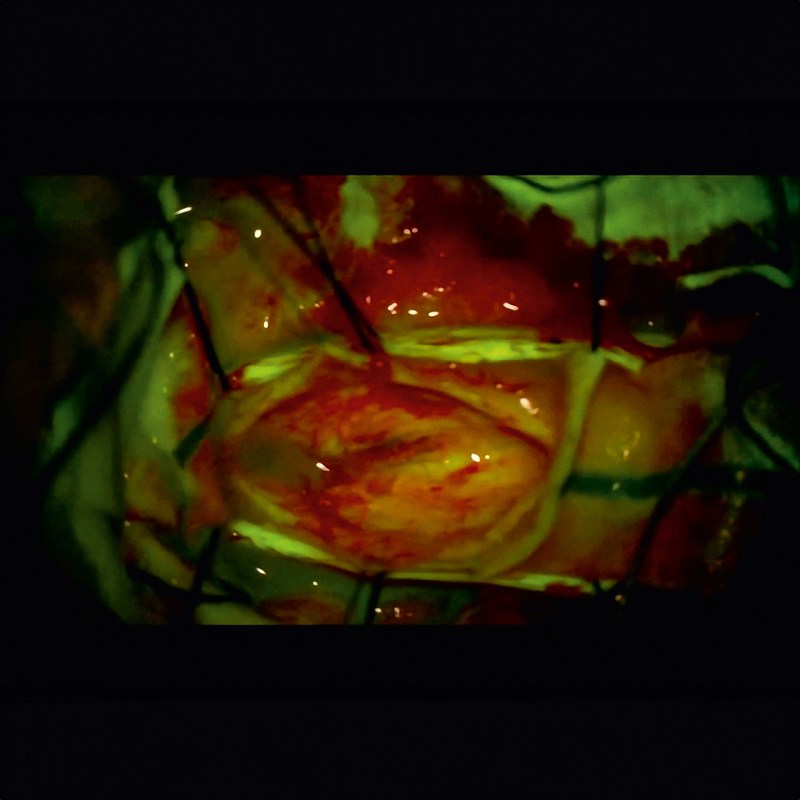

Воспользуйтесь возможностями флуоресцентной визуализации. Превосходная апохроматическая оптика ZEISS позволяет пробовать новые методы, например флуоресцентную визуализацию.

С помощью модуля инфракрасной визуализации ZEISS INFRARED 800 можно оценить проходимость сосудов, соединенных анастомозом. Модуль ZEISS YELLOW 560 расширяет диапазон клинических применений за счет визуализации анатомических структур.